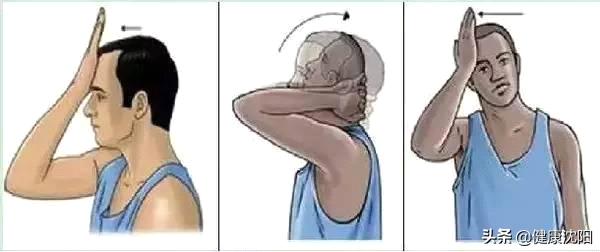

◆加强颈肩部肌肉力量的锻炼,如颈部保健操就是比较好的颈肩腰背部肌肉锻炼的运动方式。

具体方法有:尽量收缩双侧肩膀,坚持10秒左右,重复6-10次。

一手扶住前额,给予一定的阻力,抗阻力下向前屈曲颈部,坚持10秒左右,重复3-5次。

双手十指交叉抱头,给予一定的阻力,抗阻力下使头部向后仰伸,坚持10秒左右,重复3-5次。

一手扶头侧部,给予一定的阻力,抗阻力下侧屈颈部,坚持10秒左右,左右交替,重复3-5次。